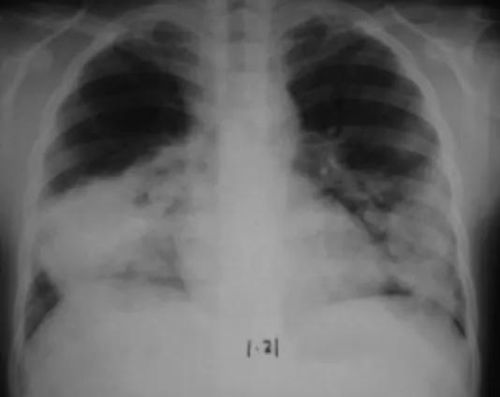

这百草枯啊, 毒性大得hen,要是进了人体,就会在肺、肝、胃这些地方捣乱。主要是氧化反应,把肺部的细胞给破坏了ran后肺部就纤维化了。这可是个慢性毒害,一开始可Neng没什么感觉,时间久了肺就不好了。